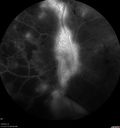

Proliferative Diabetic Retinopathy - NVD regressed with PRP laser - Prior to initial laser398 views76 year old diabetic man - Presented one year ago with NVD in the left eye. This regressed with laser but then a year later worsened. Additional PRP was done and the NVD regressed again.Jun 02, 2017

Proliferative Diabetic Retinopathy - NVD regressed with PRP laser - Regression following Initial PRP laser412 views76 year old diabetic man - Presented one year ago with NVD in the left eye. This regressed with laser but then a year later worsened. Additional PRP was done and the NVD regressed again.Jun 02, 2017

Proliferative Diabetic Retinopathy - NVD regressed with PRP laser - Recurrence one year after initial laser339 views76 year old diabetic man - Presented one year ago with NVD in the left eye. This regressed with laser but then a year later worsened. Additional PRP was done and the NVD regressed again.Jun 02, 2017